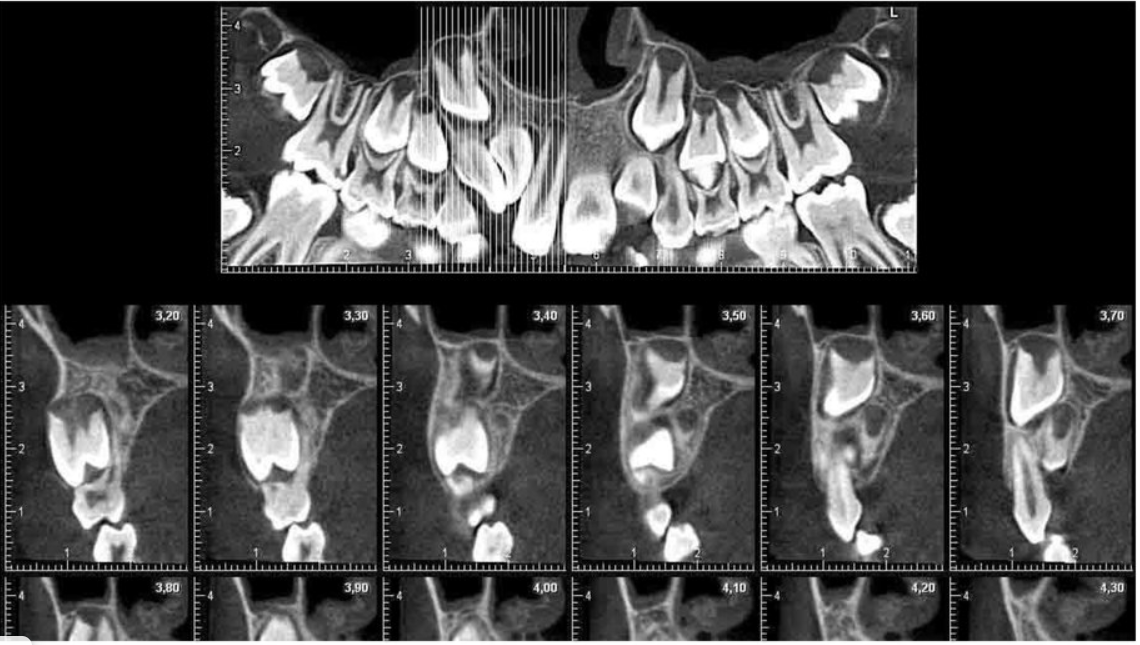

· Компьютерная томография (КТ) – трехмерное изображение зубочелюстной системы, позволяющее детально изучить структуру костей и зубов.

· Ортопантомограмма (ОПТГ) – панорамный снимок обеих челюстей, показывающий все зубы, корни, альвеолярные отростки и соседние анатомические структуры.